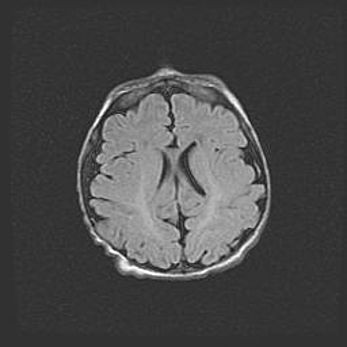

Наружная гидроцефалия с возможной атрофией височных областей.

Возраст: 28 дней

Гидроцефалия головного мозга у новорожденных – это заболевание, которое характеризуется скоплением избыточного количества спинномозговой жидкости в желудочковой системе головного мозга в результате затруднения её перемещения от места выработки к месту поглощения в кровеносную систему или вследствие нарушения абсорбции. При открытой наружной форме гидроцефалии у новорожденных расширяются и переполняются субарахноидные пространства.

При нормотензивных  формах,  которые,  как  правило,  являются  следствием  перенесенных ишемических  повреждений  паренхимы  мозга,  возможно  сочетание микроцефалии  с нормотензивной гидроцефалией. В основе данных изменений лежит атрофия больших полушарий с преимущественной  локализацией  в  лобно-височных  областях.